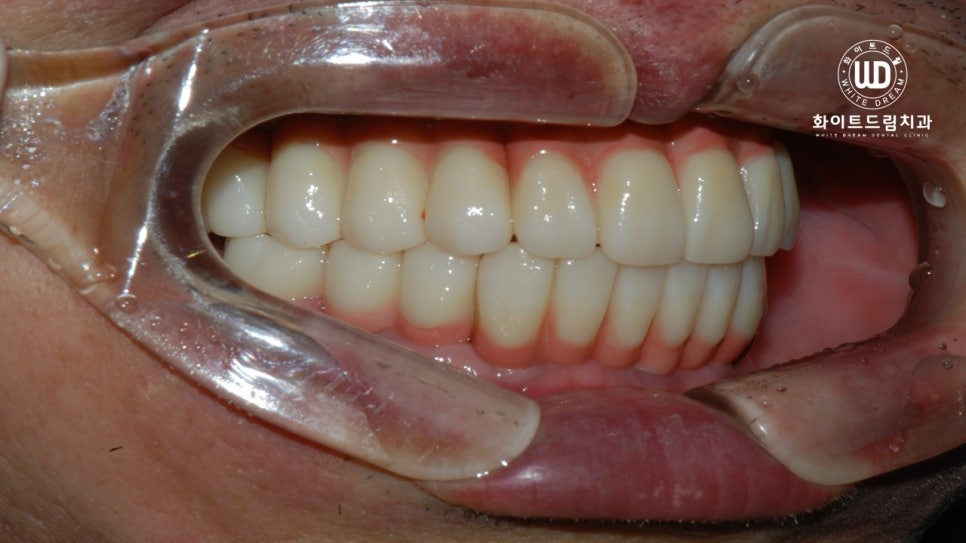

다음은 상악동 거상술과 치조골이식술을 동반한 임플란트 식립 후 최종 진단 결과물입니다.

좌측에 보이는 사진이 임플란트 치료 전 모습이며, 우측이 치료 후 모습입니다.

이전의 구강상태와 확연한 차이를 보이고, 구강 저작력이 크게 향상되는 등 만족스러운 결과가 나왔습니다.

치료가 완료된 사진을 살펴보면 임플란트가 뿌리부터 머리까지 나란히 매끄럽게 연결되어 있는 것을 확인하실 수 있는데, 상악 하악의 U자 형태가 본 케이스와 같이 나올 수 있으려면 임플란트 보철 식립 방향을 잘 체크해야합니다.

환자분께서 부분틀니를 사용하다가 전체 임플란트를 진행하게 됐는데, 훨씬 더 편안하고 음식을 씹는데 큰 문제가 없어 만족한다는 말씀을 전해주신 것이 기억에 남습니다.